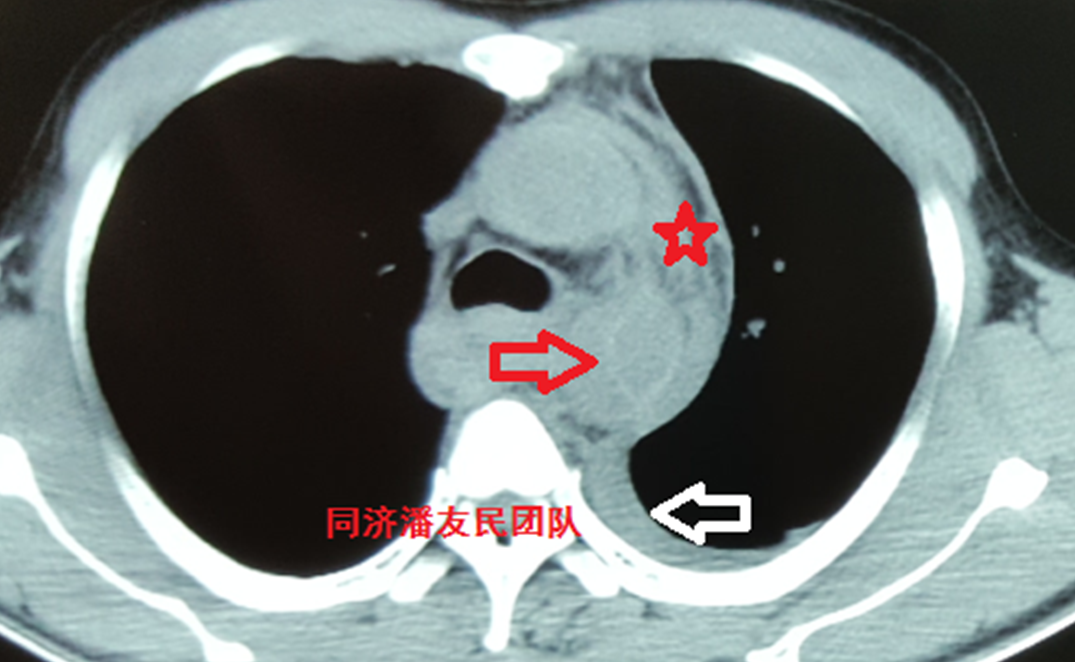

由于病人本身没有主动脉基础病变,而当外力作用相对较弱时,主动脉夹层的撕裂比较局限,仅仅累及一小段胸降主动脉,这种特征性的影像学改变是外伤性主动脉夹层特有的。

除了局限性主动脉夹层外,也可以表现为非局限性夹层,即普通类型的降主动脉夹层(图6)。

图6 左图为局限性外伤性主动脉夹层(白箭头所示)。右图为非局限性外伤性主动脉夹层。

外伤性主动脉夹层从影像学表现分两种情况:局限型和非局限型;